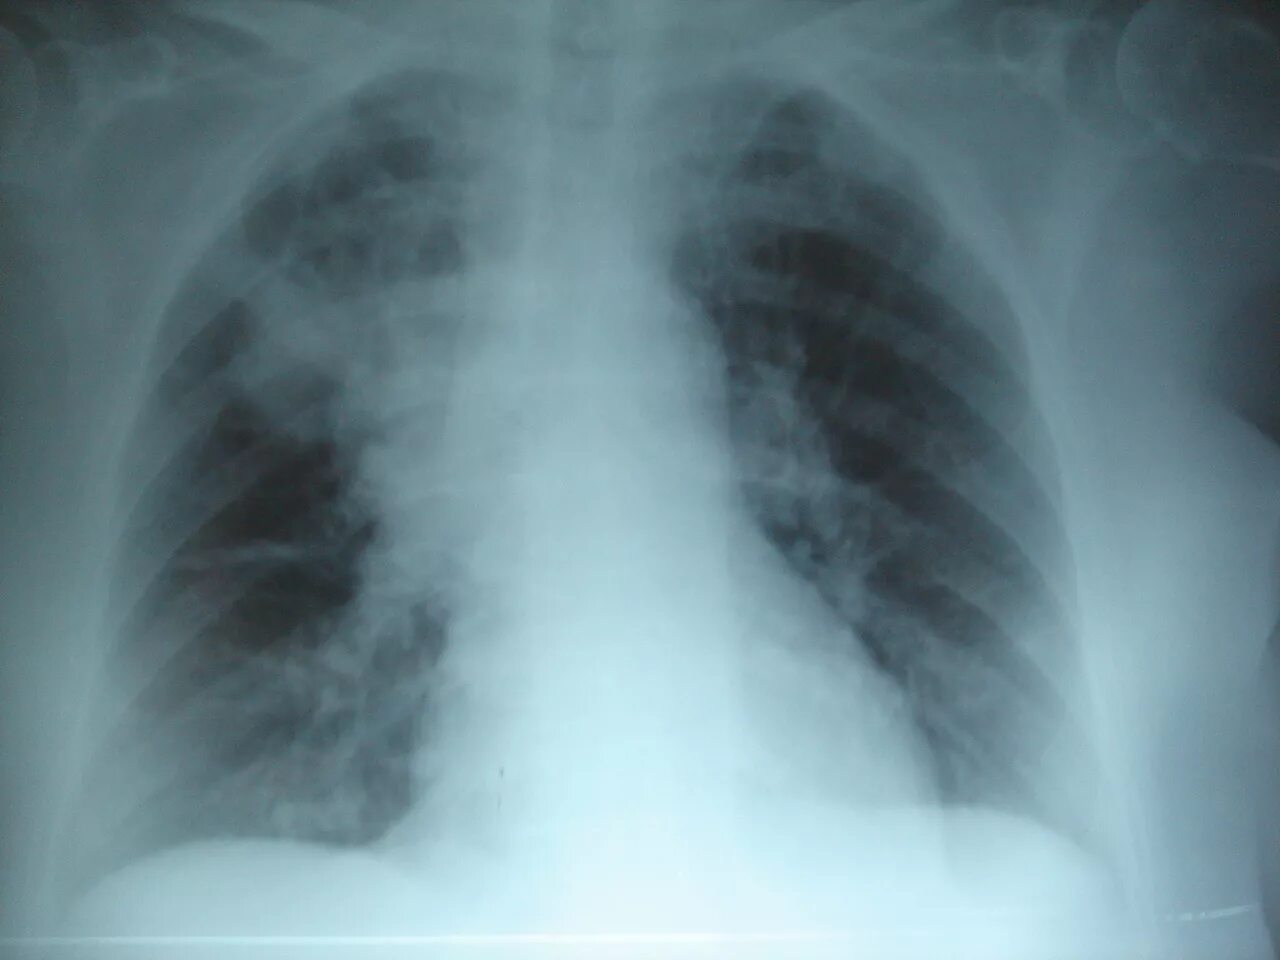

Двух воспаления легких